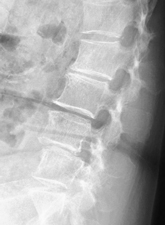

せぼねの変形や椎間板の傷み具合、不安定性の有無、脊柱管の狭さ、またせぼね全体のバランスなどを見るためにX線検査やCT検査、MRI検査などを行います。進行例では脊柱管の狭さをより詳しく評価するために入院して脊髄造影検査や、同時にどの神経が痛みの原因となっているかを明らかにするために神経の枝に直接麻酔薬を注入する選択的神経根ブロックを行う場合があります。成人期では血管性の下肢の痛みがないか評価するために両手足の血圧を測ったり、骨粗鬆症の有無を評価するために骨密度検査を行うこともあります。

せぼねの変形や椎間板の傷み具合、すべりや不安定性の程度、脊柱管の狭さ、またせぼね全体のバランスなどを見るためにX線検査やCT検査、MRI検査などを行います。進行例では脊柱管の狭さをより詳しく評価するために入院して脊髄造影検査や、同時にどの神経が痛みの原因となっているかを明らかにするために神経の枝に直接麻酔薬を注入する選択的神経根ブロックを行う場合があります。成人期では血管性の下肢の痛みがないか評価するために両手足の血圧を測ったり、骨粗鬆症の有無を評価するために骨密度検査を行うこともあります。

せぼねの変形や椎間板の傷み具合、すべりや不安定性の有無、脊柱管の狭さ、またせぼね全体のバランスなどを見るためにX線検査やCT検査、MRI検査などを行います。進行例では脊柱管の狭さをより詳しく評価するために入院して脊髄造影検査や、同時にどの神経が痛みの原因となっているかを明らかにするために神経の枝に直接麻酔薬を注入する選択的神経根ブロックを行う場合があります。成人期では血管性の下肢の痛みがないか評価するために両手足の血圧を測ったり、骨粗鬆症の有無を評価するために骨密度検査を行うこともあります。